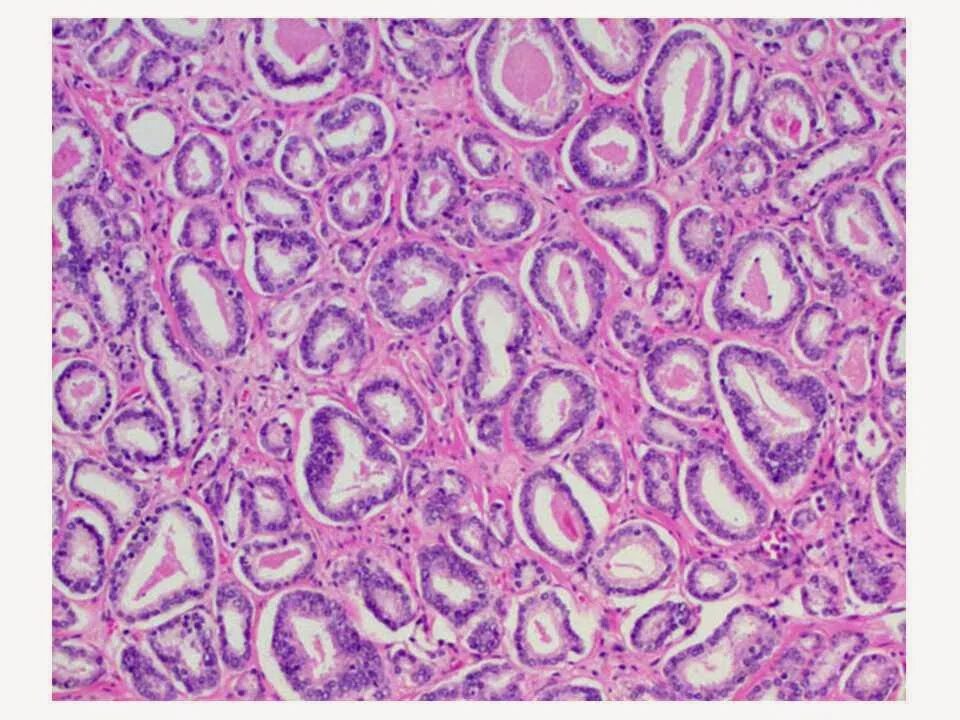

Глисон простата